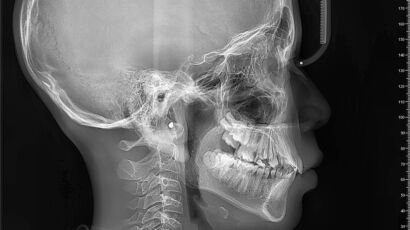

Un examen de tomografía computarizada (TAC) macizofacial es una herramienta diagnóstica esencial en la…

El examen de TAC macizofacial, o tomografía axial computarizada macizofacial, es una técnica de…